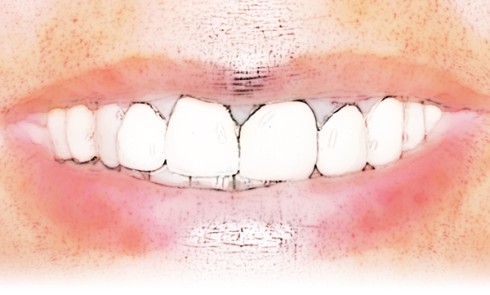

Article réservé à nos abonnés Ma première « three step technique » – partie 2

Une fois le projet esthétique et fonctionnel validé grâce aux full mock-up en résine [4], nous procédons à la réalisation...